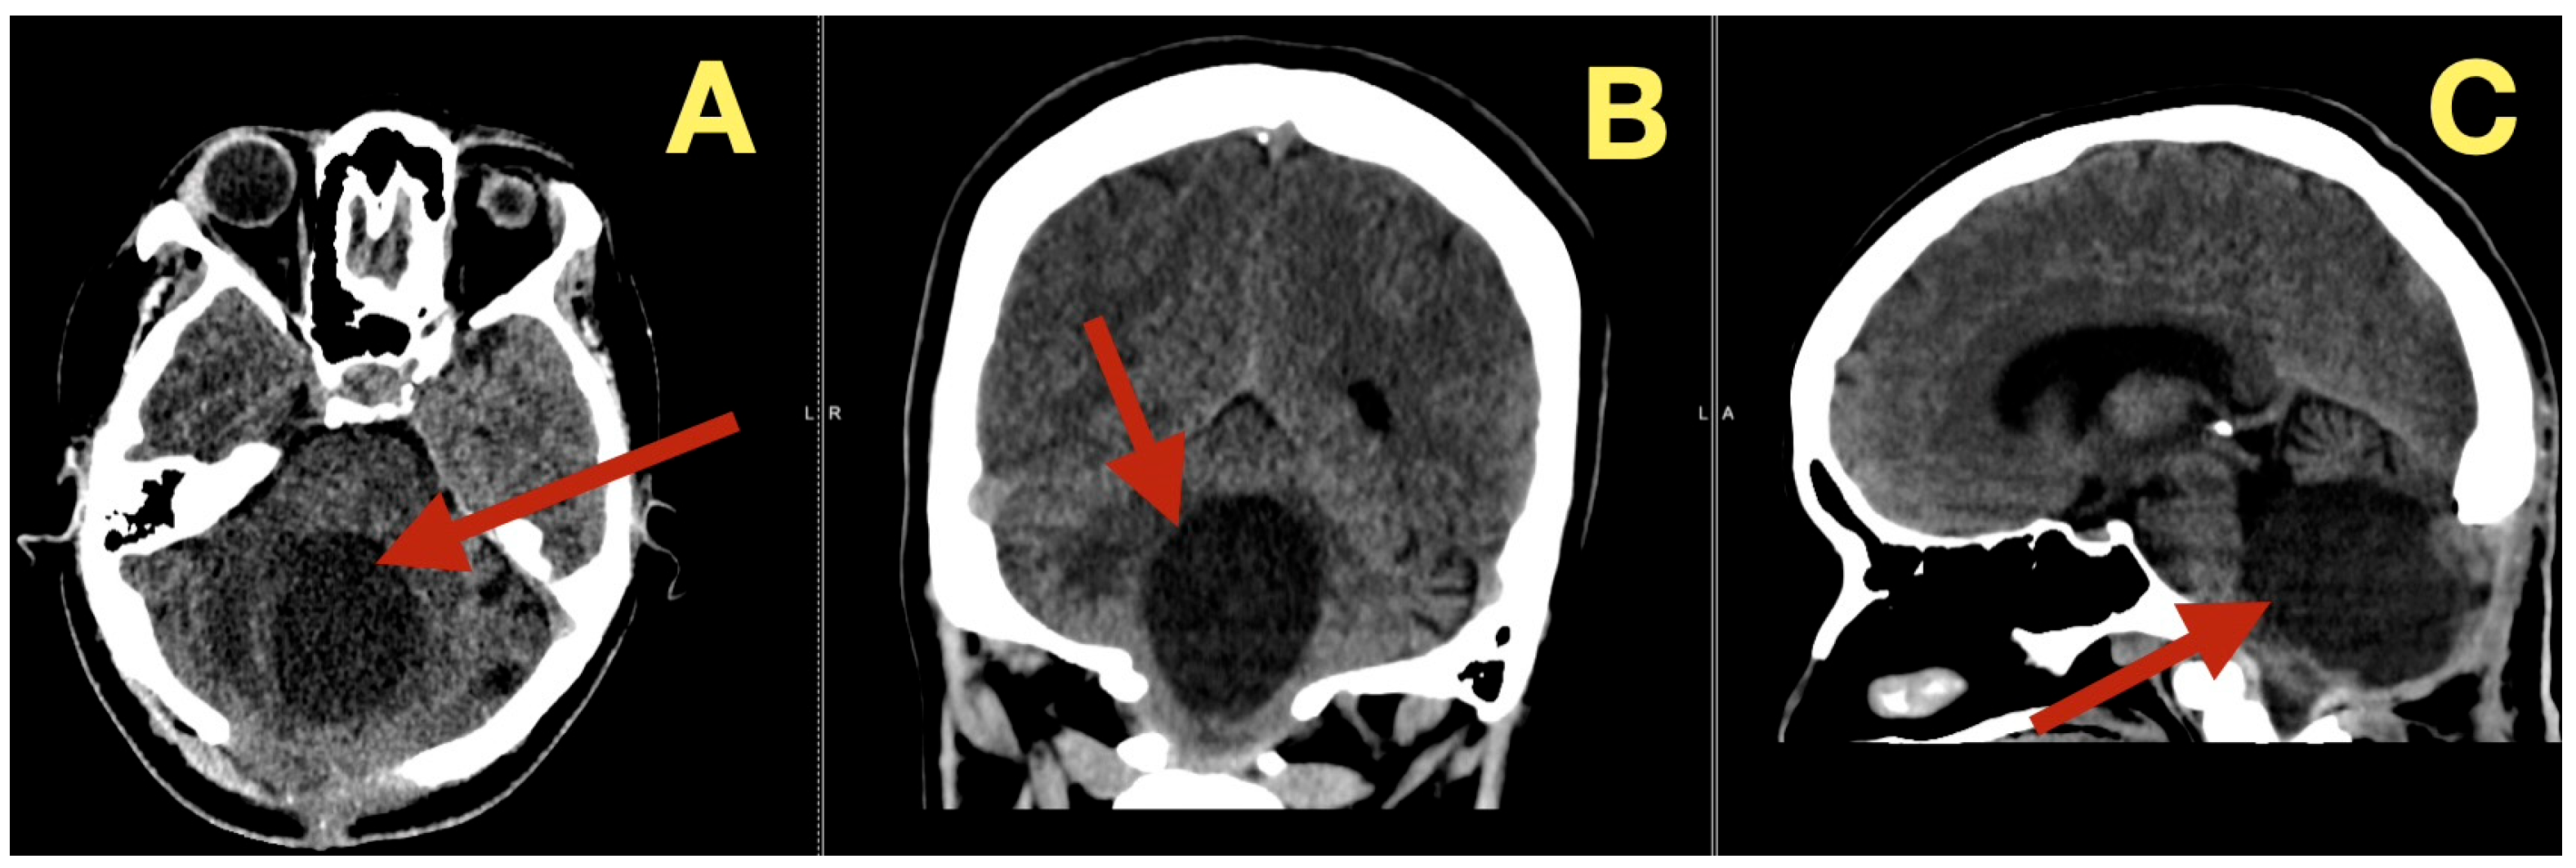

CT scans seven months after surgery (Figure 8), demonstrated long term stability: the fourth ventricle remained widely patent, the posterior fossa proportions were normal, the CSF spaces were symmetric, and there was no evidence of recurrence, new calcification, subdural collection, or ventricular change. Clinically she remained neurologically intact, describing stable gait and effortless balance. Final scores were MRS = 0, SARA = 1/40, and she returned to work and daily activity.

Figure 8.

Seven-month postoperative CT scan. (A): Axial CT showing persistent decompression of the fourth ventricle and normal CSF distribution (arrow). (B): Coronal CT demonstrating stable midline anatomy and unchanged posterior-fossa dimensions with no residual lesion (arrow). (C): Sagittal CT confirming complete restoration of brainstem and cerebellar geometry, maintained CSF flow, and absence of new pathology (arrow).